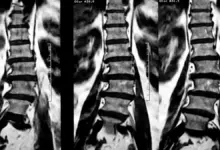

- Ressonância magnética: mostra compressão, edema e sofrimento medular.